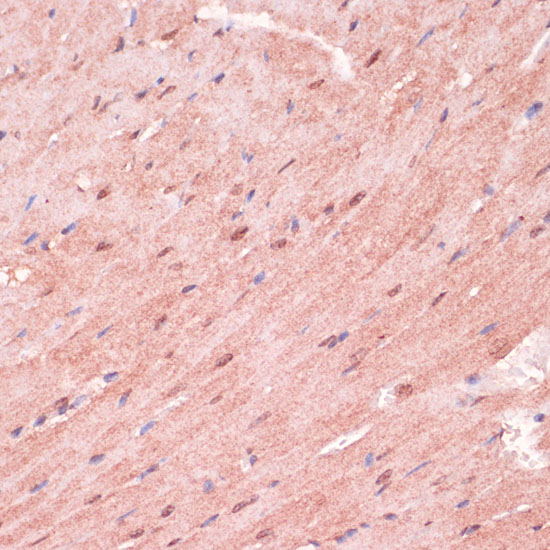

Immunohistochemistry of paraffin-embedded mouse heart using RNF5 at dilution of 1:100 (40x lens).